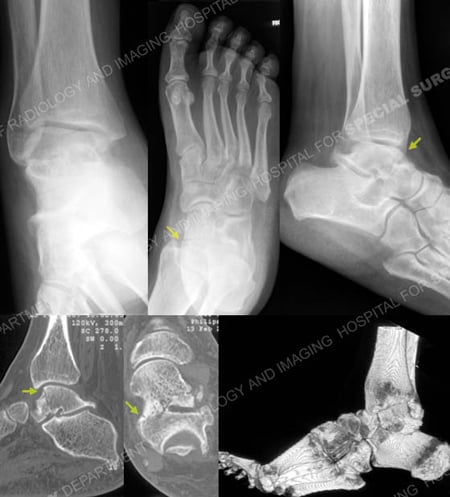

Anteroposterior, Canale and lateral radiographs revealing a talus fracture (arrows). CT scan images further delineating the talus fracture pattern (arrows).